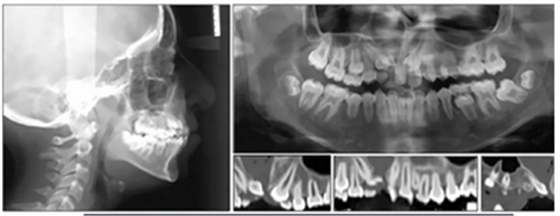

全景片示:側(cè)切牙扭轉(zhuǎn)、發(fā)育異常,影響上頜左側(cè)尖牙,下頜左側(cè)第二磨牙嚴(yán)重近中傾斜。幾乎所有的牙齒都是短根,但沒有觀察到牙根吸收的現(xiàn)象。

頭部側(cè)位片測(cè)量顯示骨性I類錯(cuò)合畸形(ANB,3.5°),垂直生長(zhǎng)模式(SN / GoMe,39°),上頜中切牙后傾(1 / SN,94°)和下頜中切牙前傾(IMPA,100 °)(圖3)。